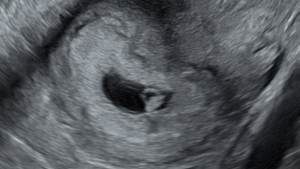

The Benefits of Transvaginal Ultrasounds in Early Pregnancy

Discover the benefits of transvaginal ultrasounds in early pregnancy, why they’re recommended before 10 weeks, and learn why they are safe for both mum and baby.